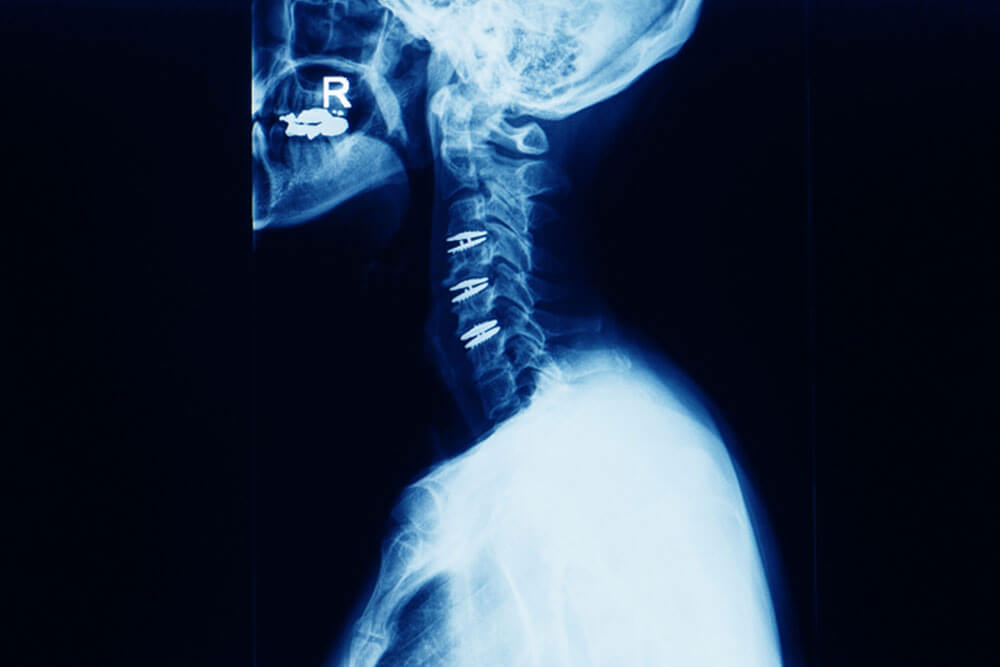

"Hello, I'm Hannan. I was involved in a highway accident on June 12, 2022, which resulted in a serious traumatic spinal injury. After receiving first aid and undergoing further examination at the hospital, my family and I decided to consult Dr. Saad Akhter for my spinal surgery. Following a period of observation and treatment, I was discharged from the hospital with a recommendation for six months of bed rest. However, I made an exceptional recovery within four months and was able to fly abroad for a new job. Alhamdulillah, I've been fortunate enough to not experience any significant hurdles or pain throughout my journey so far. I do take necessary precautions to protect my health and spinal well-being. I'd like to express my gratitude to Dr. Saad Akhter for his kindness, support, and expert care. I highly recommend him for any neurological or related treatments - 100%!"